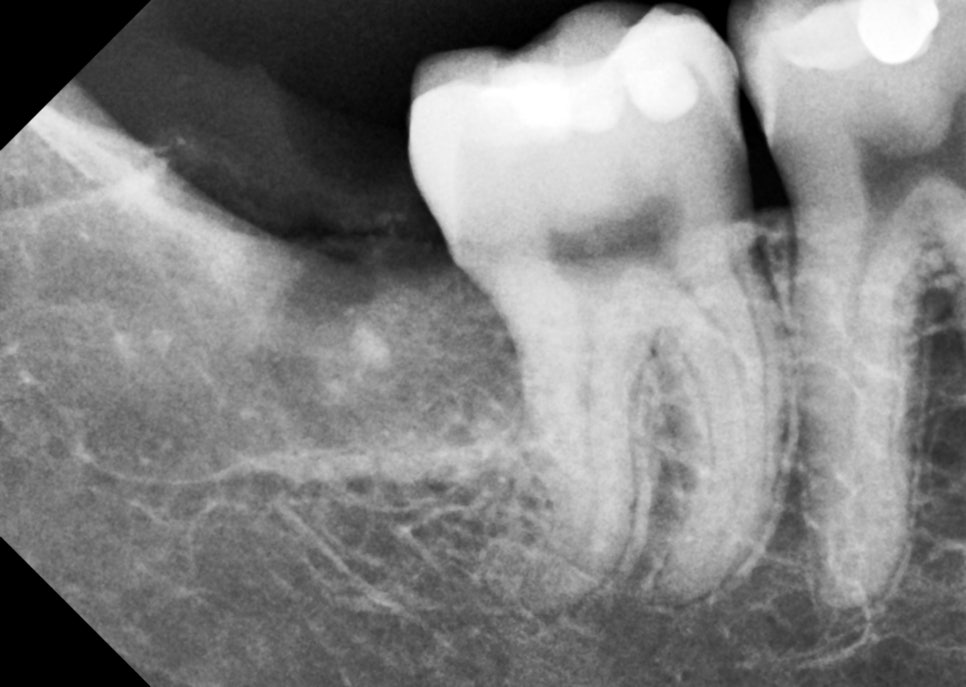

촬영일 : 251121 / 251201

환자가 덜 아프고, 덜 붓고, 회복이 편한 쪽으로 가는 게 제 기준이에요.

이번 케이스도 그 기준 안에서 진행했어요. 매복의 경우 잇몸을 절개할 수밖에 없기 때문에 절개 범위를 줄이고 뼈 삭제도 줄인 것처럼 말이죠ㅎㅎ